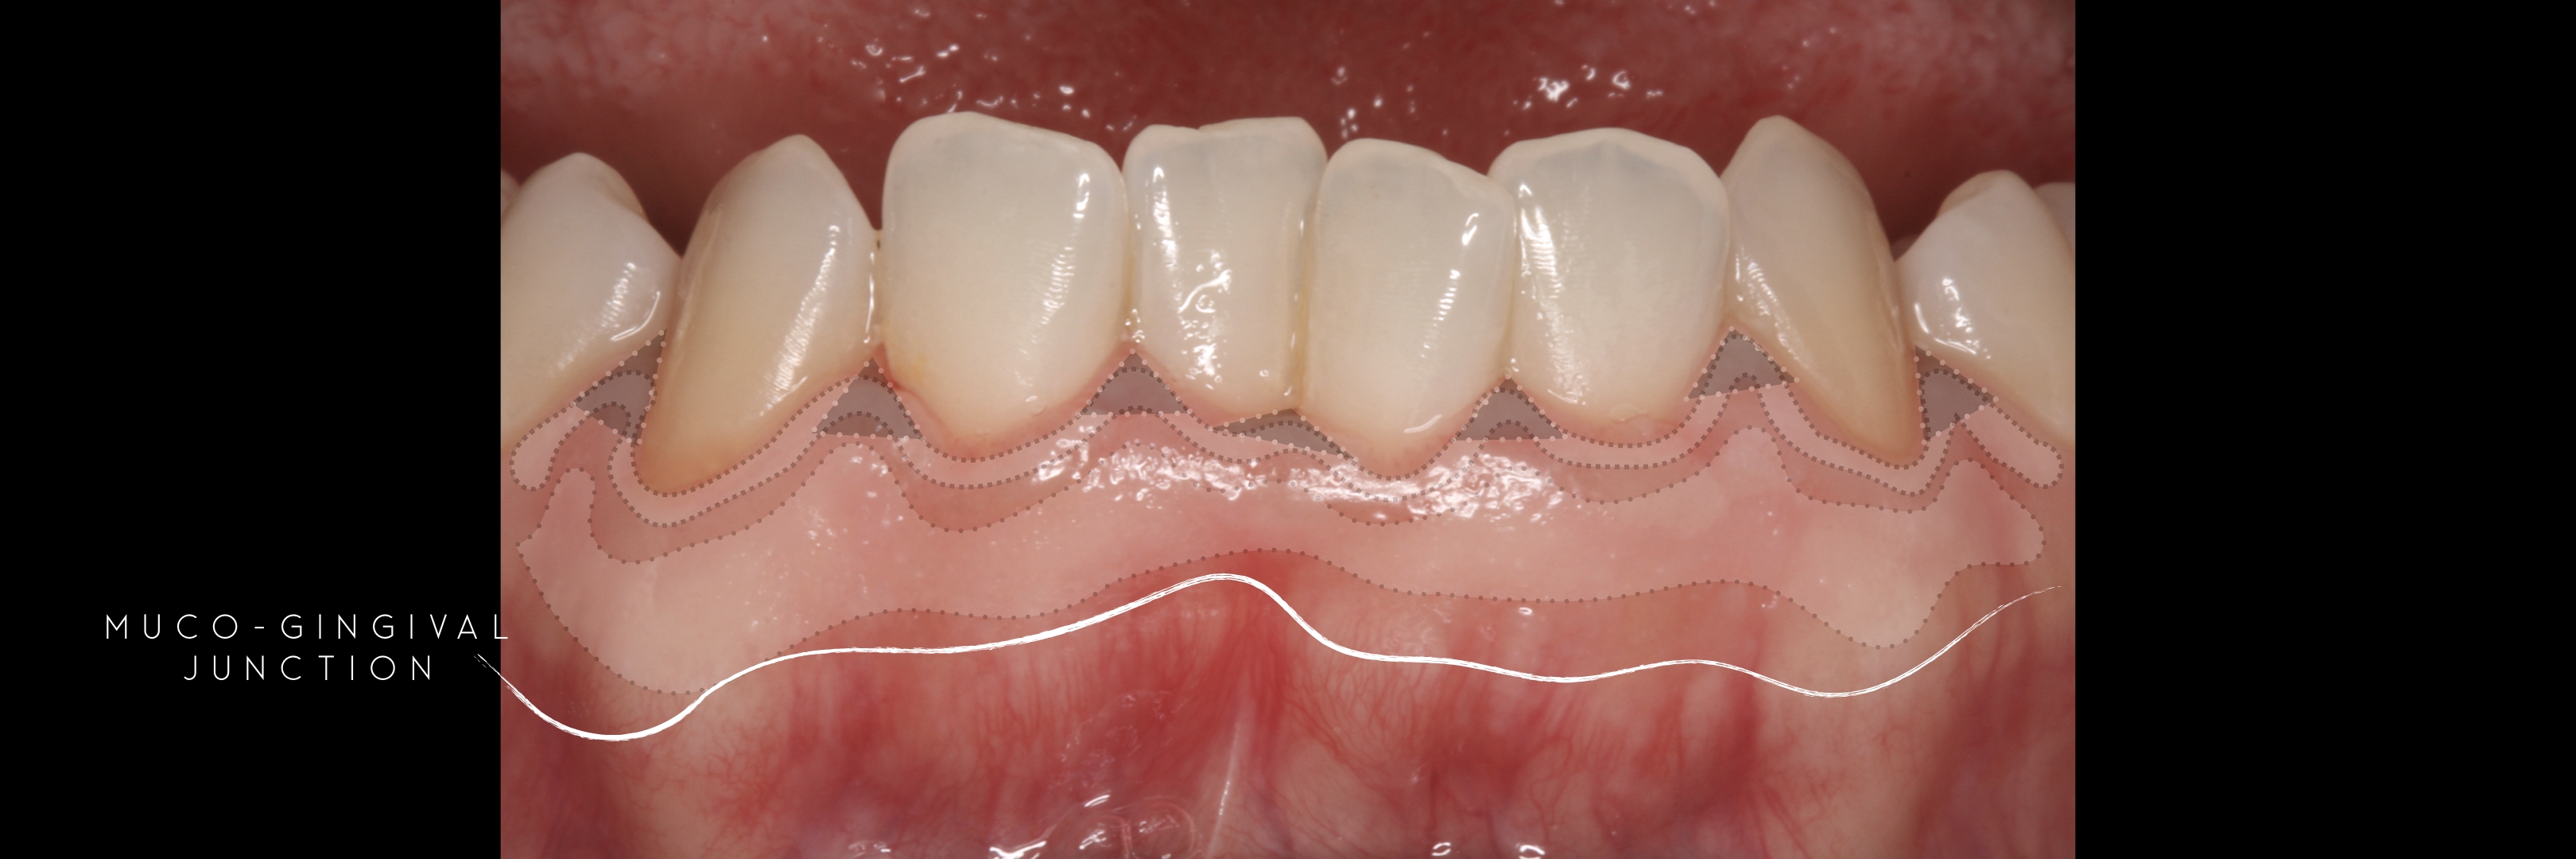

and the attached gingiva extending from the gingival mar­gin to the mucogingival junction.

The width of the keratinized gingiva may vary between 1 and 9mm.

Bowers, G.: A study of the width of attached gin­ giva. J. Periodont. 54:201-209, 1963.

Ainamo, J. and Löe, H : Anatomical characteristics of gingiva. A clinical and microscopic study of the free and attached gingiva. J. Periodont. 57:5-13, 1966.

However, the question of how much gingiva is "adequate" has still not been investigated.

There was no answer at the time of Lang and Löe's paper -1972 - and still nowadays we still lack a final answer, but attached gingiva plays a major role on stable soft tissues around teeth and implants.